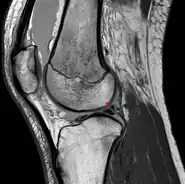

The Posterior meniscofemoral ligament (also known as the ligament of Wrisberg) is a small fibrous band of the knee joint. It attaches to the posterior area of the lateral meniscus and crosses superiorly and medially behind the posterior cruciate ligament to attach to the medial condyle of the femur.[1]

The posterior meniscofemoral ligament is found in 64.4% of the subjects in MRI scan of the knee.[1]